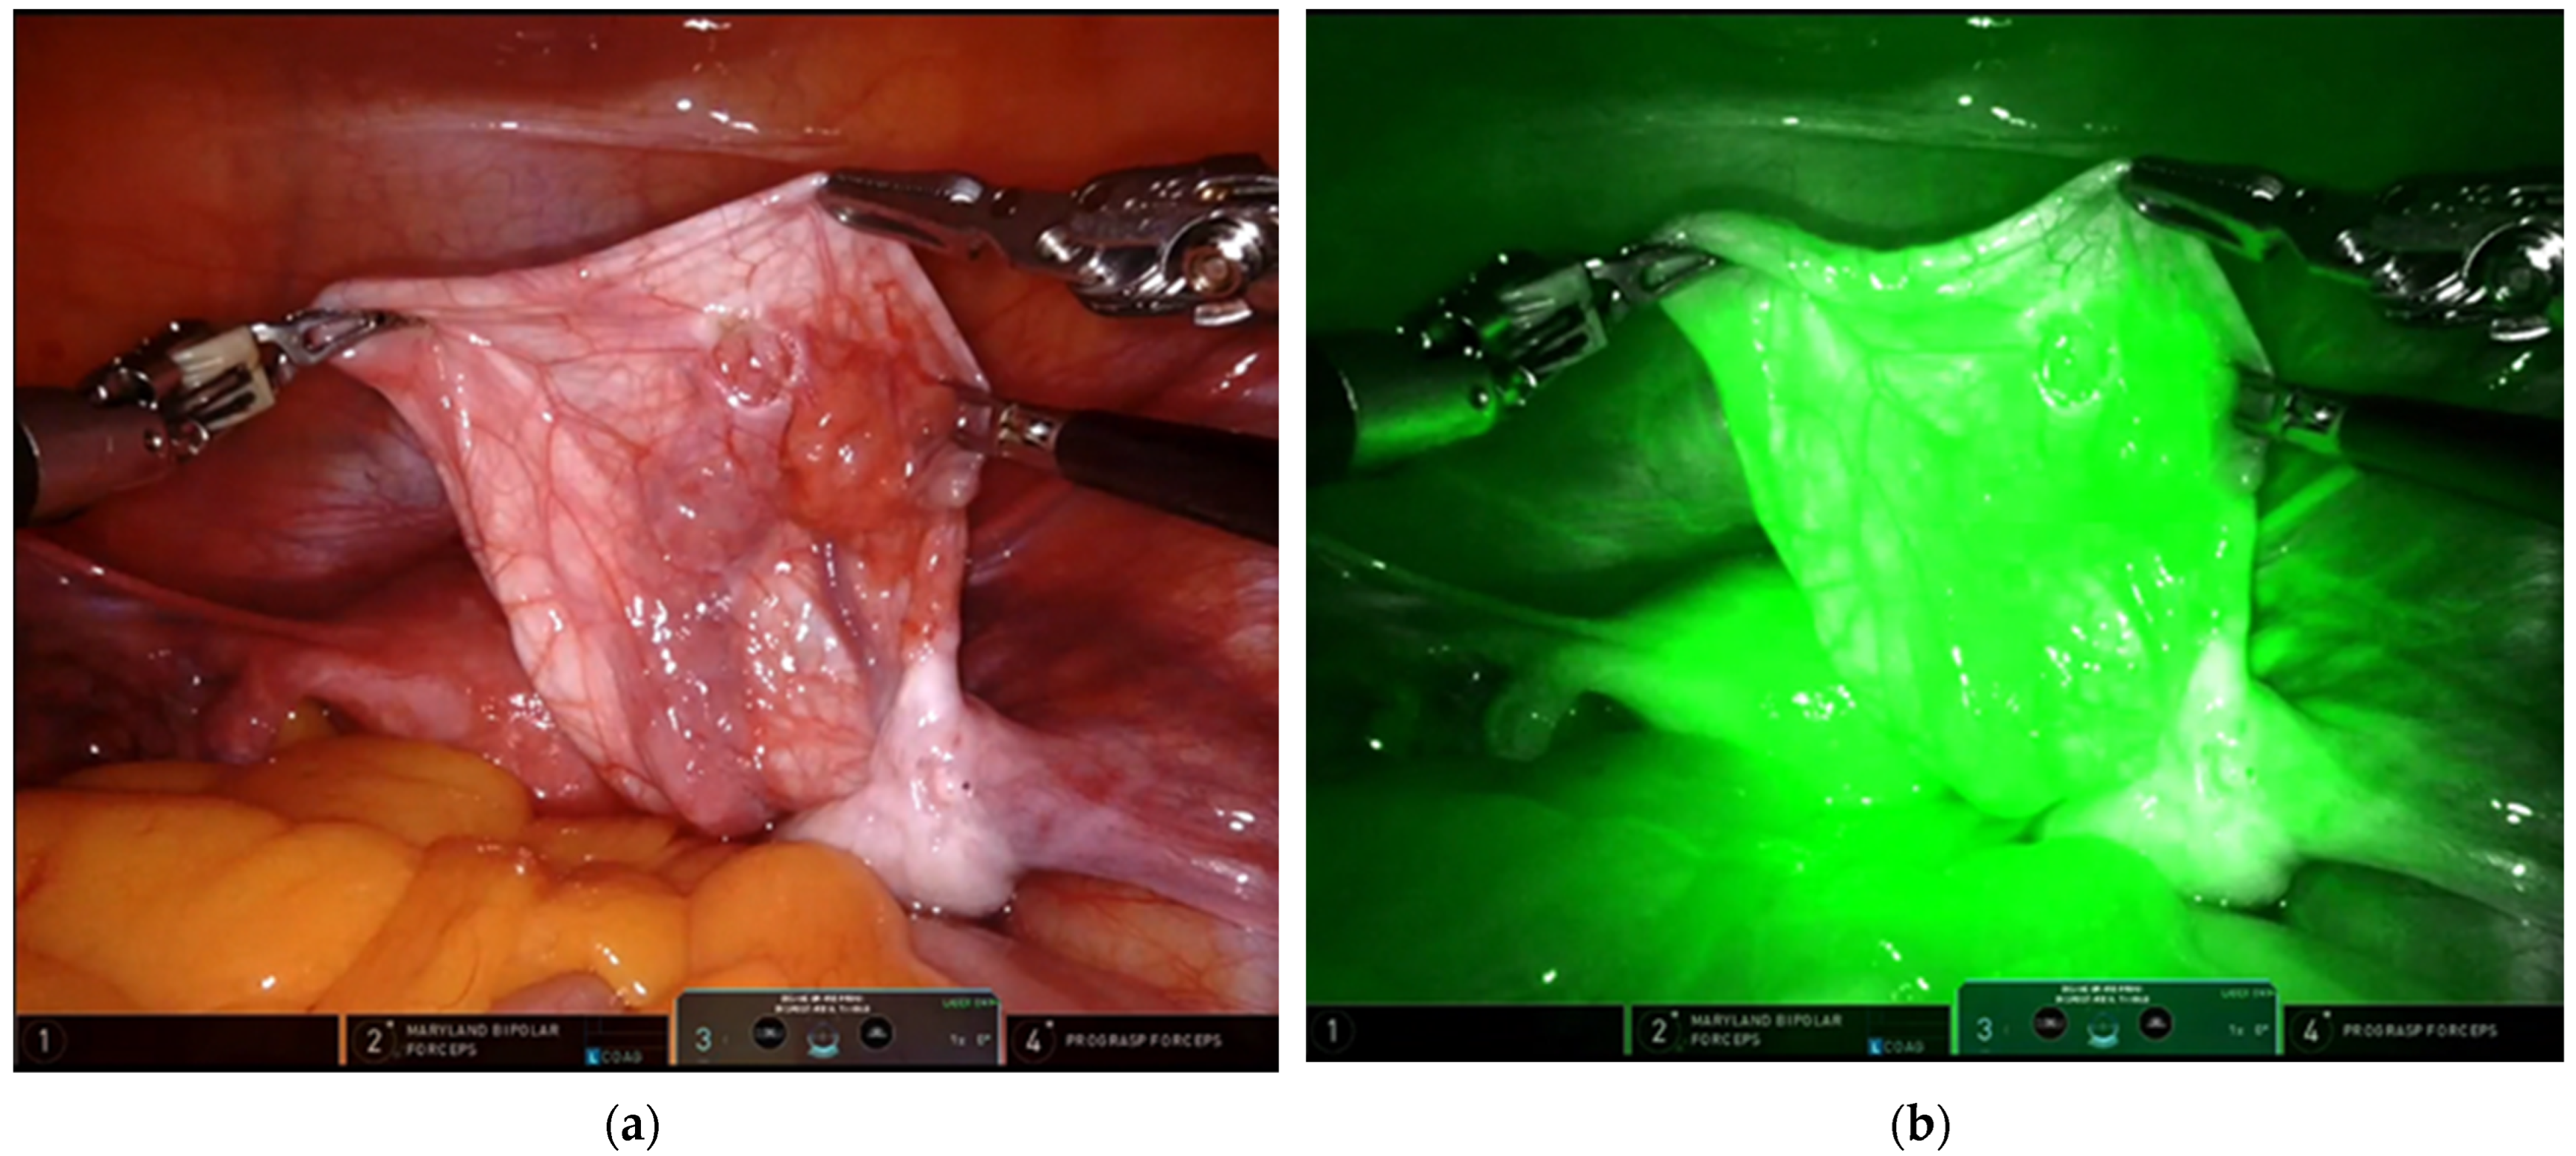

- Esposito, C.; Coppola, V.; Del Conte, F.; Cerulo, M.; Esposito, G.; Farina, A.; Crocetto, F.; Castagnetti, M.; Settimi, A.; Escolino, M. Near-Infraredfluorescenceimagingusingindocyanine green (ICG): Emergingapplications in pediatricurology. J. Pediatr. Urol. 2020, 16, 700–707. [Google Scholar] [CrossRef]